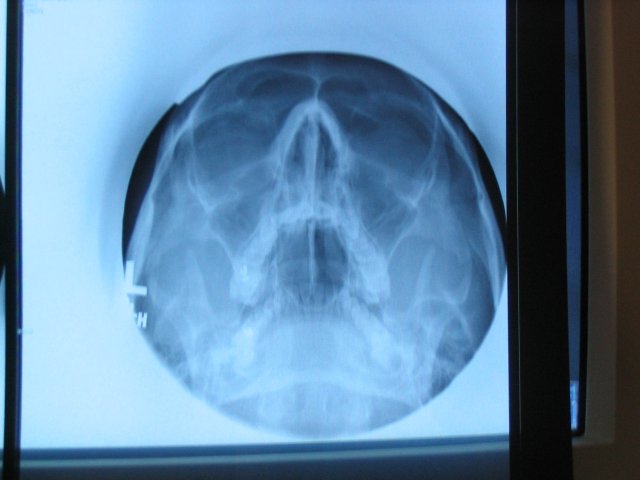

The sore throat is all but gone today, but I woke up this morning not able to hear out of my left ear. Every I/O cavity in my head is so screwed up it's not even funny. I've already been on a bunch of different medications, all unsuccessful, so I'm not entirely sure where we're going from here. Last time I went to my doctor he mentioned x-rays being the next step, so today he took a look and a listen, and sent me next door for x-rays. I asked the technologist what it would take for me to get a copy of my x-rays, and she asked why I wanted them. "Because I want them" was reason enough for me, but was not good enough according to her. I replied "It's going to have to be." Needless to say, I went home with a copy of my x-rays.

The one where I'm looking up with my mouth open is awesome.

I'm feeling a bit better, though the past few days I've been waking up with headaches. Doctor thinks my throat problem is consistent with Sinusitis, so we're moving from there. We'll see.